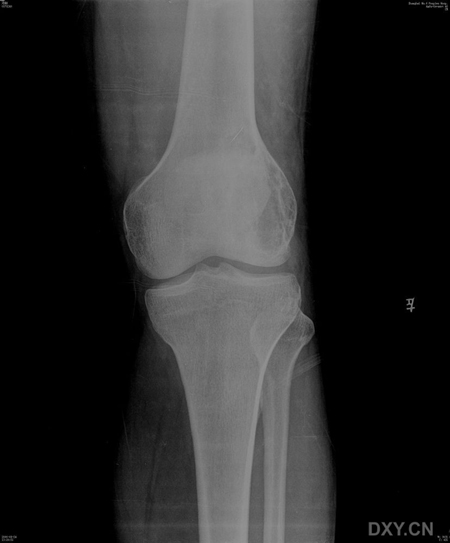

患者,男,38岁,左膝疼痛半月,体检左膝无红肿,无其它既往史

病灶最大径与骨干垂直,病灶呈侵袭性生长,病灶内未见钙化及骨化影,未见骨膜反应,未见软组织肿块,骨壳尚完整.考虑骨巨(良性).

左侧股骨外侧髁囊性低密度灶 考虑 1 骨巨细胞瘤 2 骨囊肿不除外.

骨巨细胞瘤:病变位于骨端,偏心性分布,其内密度均匀,边缘无硬化,无骨膜反应,无软组织肿块,体检左膝无红肿,无其它既往史,及高发年龄

病灶最大径与骨干垂直,病灶呈侵袭性生长,病灶内未见钙化及骨化影,未见骨膜反应,未见软组织肿块,骨壳尚完整.无硬化边.考虑骨巨(良性).

支持骨巨细胞瘤(病灶偏心性生长,无骨化、钙化及骨膜反应,无软组织肿块,内见纤细间隔)。

ct图片太少,x光片示肿瘤呈横向生长,其内可见纤细分隔,符合骨巨的特点,年龄也符合。